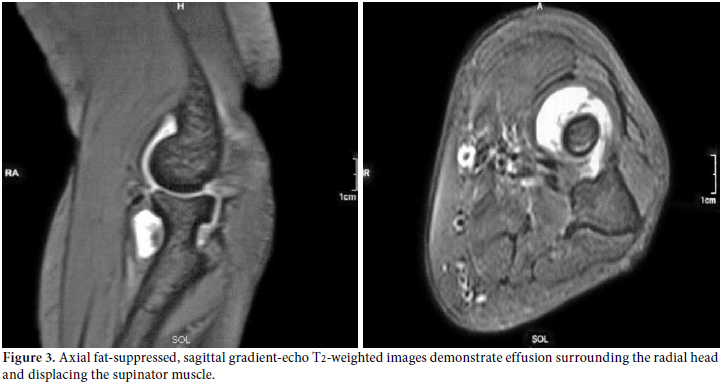

Plain radiography of the left elbow, musculoskeletal ultrasonography (US), and magnetic resonance imaging (MRI) were used to make a visual representation of the pathology. The plain radiography showed soft tissue swelling with a normal articular surface. The US assessment (7.5 MHz linear transducer, gray scale, General Electric Medical Systems, Milwaukee, Wisconsin, USA) pointed out an “eye-shaped”, demarcated, hypoechoic bulging mass with regard to articular effusion that was in close contact with the “contoured eyebrow-shaped” fascicular PIN. It had swelled to 2 mm compared with 1 mm on the asymptomatic right side (Figure 2). The MRI indicated hyperintense, demarcated fluid around the radial head, neck, and distal humerus (Figure 3).

The diagnostic approach, including a careful clinical examination, non-invasive imaging techniques (US, MRI), and electrophysiological assessment were sufficient to obtain the diagnosis of PIN palsy. The patient refused to be assessed surgically, so we reconsidered and rearranged her medication by increasing the methotrexate dosage to 15 mg/week and also subcutaneously, drained the fluid and injected methylprednisolone acetate (40 mg/mL) intra-articularly by using the lateral approach to the center of the triangle formed by the lateral olecranon, the head of the radius, and the lateral epicondyle.[7] The patient was followed up via clinical, US and electrophysiological assessments every three months. Her symptoms improved the second month after the injection, and they completely resolved at the sixth month without surgical intervention. The ultrasonographic resolution was noted at the third month, but better recruitment was obtained at sixth month from the affected muscles. However, fibrillation potentials remained albeit with a smaller amplitude size. Revisualization by MRI, repeated at the 18th month, detected resolved effusion with clinical stability (Figure 4).